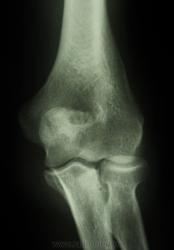

Пол пациента: Мужской пол Тип патологии: Травма Область исследования: Скелетно-мышечная система Методы исследования: Rg Мужчине 47 лет. Травма. Просьба помочь с оценкой диастаза и состояния спиц по отношению к суставной щели - удовлетворительно ли? https://radiomed.ru/sites/default/files/styles/case_slider_image/public/user/6152/2-l.jpg?itok=tUE8E8hs https://radiomed.ru/sites/default/files/styles/case_slider_image/public/user/6152/3-l.jpg?itok=PBUd5TE2 https://radiomed.ru/sites/default/files/styles/case_slider_image/public/user/6152/4-l.jpg?itok=5xNqf1J8 ID:7680 Wed, 06/10/2010 - 12:26 #1 Vega Offline Last seen: 4 months 3 weeks ago Joined: 22.01.2009 - 19:16 Posts: 1087 Удовлетворительно. Wed, 06/10/2010 - 12:32 #2 Александр Викторович Offline Last seen: 8 years 5 months ago Joined: 31.07.2010 - 13:05 Posts: 639 Ну, близко к удовлетворительному. Wed, 06/10/2010 - 13:27 #3 Medeа Offline Last seen: 15 years 2 months ago Joined: 10.09.2010 - 18:11 Posts: 152 Спасибо! Thu, 07/10/2010 - 13:41 #4 Vikkur Offline Last seen: 5 years 3 weeks ago Joined: 24.09.2009 - 14:34 Posts: 1749 и мозолька зреет.. Виктор.

Удовлетворительно.

Ну, близко к удовлетворительному.

и мозолька зреет..